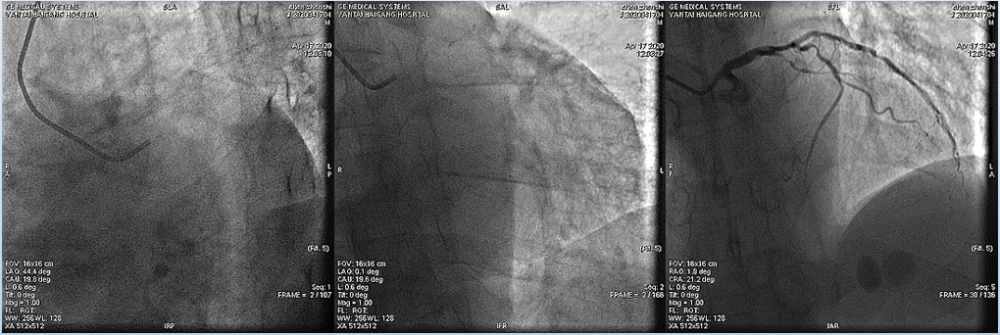

4月17日造影结果如图所示:

文章插图

冠状动脉供血为右优势型 , 冠状动脉开口正常 。 左主干未见明显狭窄;

前降支近中远段80%-99%弥漫性狭窄 , 前向血流TIMI 1级;

回旋支中段60%-70%弥漫性狭窄 , 远段可见50%弥漫性狭窄 , 前向血流TIMI3级;

右冠近中段80%-99%弥漫性狭窄 , 前向血流TIMI 2级